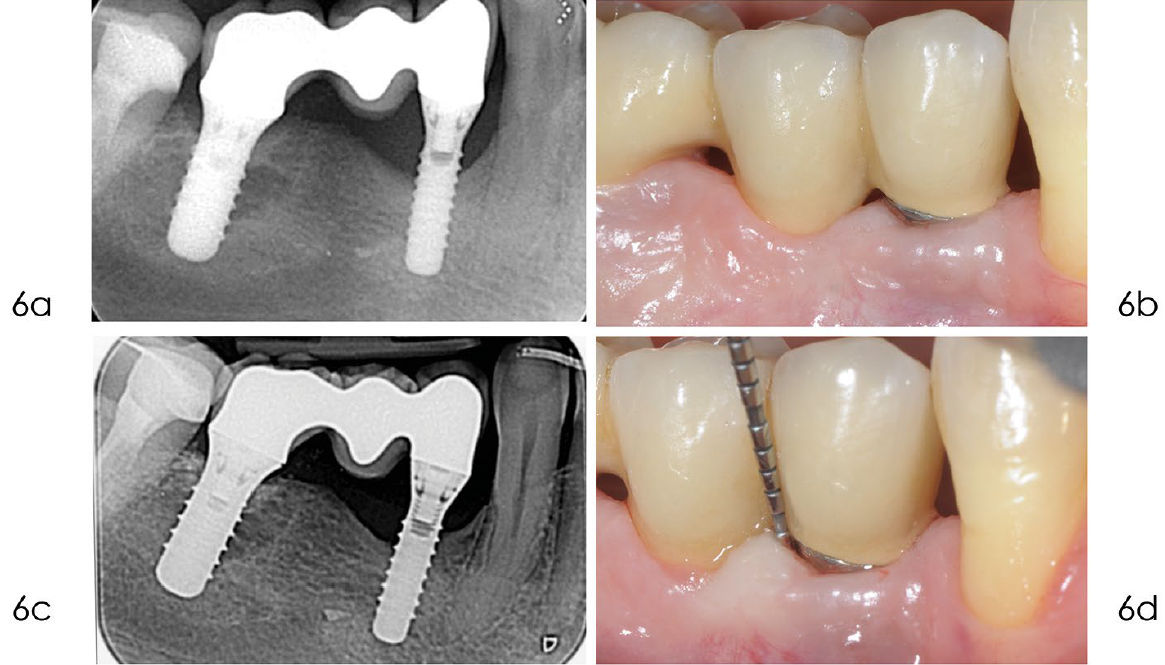

Фото 5. a) После удаления грануляционной ткани поверхность имплантата была обработана 24% ЭДТА в течение двух минут. b) После промывания физиологическим раствором на поверхность нанесён гель хлоргексидина 1% на две минуты. c) Шов нитью Vicryl 4/0 обеспечивает оптимальное открытое (непогружённое) заживление. d) Заживление проходит без осложнений

Фото 6. a) Рентгенограмма, выполненная в сентябре 2020 года, через десять лет после установки имплантата, показывает стабильный костный дефект. b) Клиническое изображение, сделанное в сентябре 2020 года, демонстрирует отсутствие воспаления в мягких тканях вокруг имплантата. c) Рентгенограмма, выполненная в январе 2024 года, подтверждает отсутствие дальнейшей потери кости дистально и небольшое улучшение с мезиальной стороны. d) Клиническое изображение, сделанное в январе 2024 года, показывает минимальную рецессию мягких тканей через 14 лет после установки имплантата. Зондирование выявляет стабильную, хотя и не идеальную, глубину пародонтального кармана